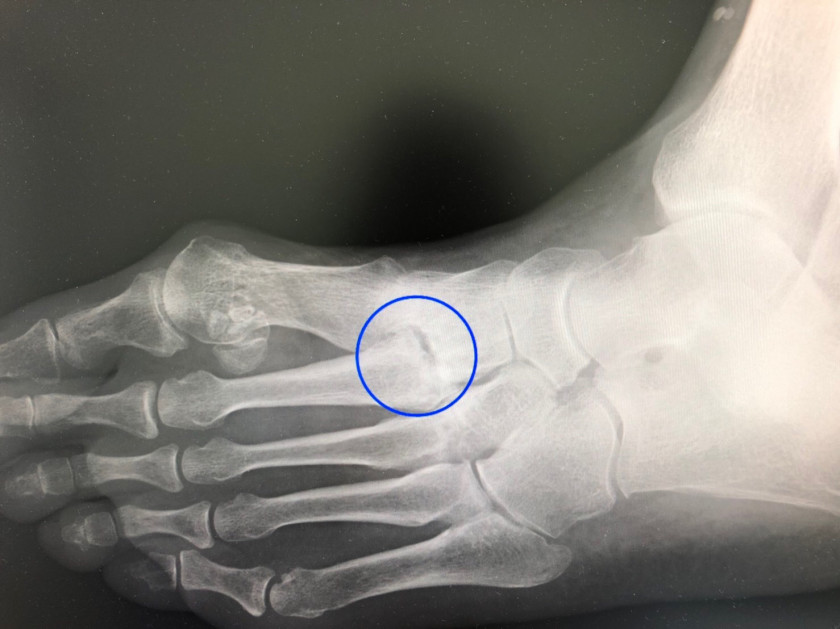

受診された患者さんです。最近、ケガをしたわけでもないのに、旧に左足の甲が痛くなり、某病院を受診。その時、医師から言われたのが冒頭(タイトル)の言葉。 患者さんが覚えていた詳細は、「レントゲンは問題有りません。湿布でも出しましょうか、どうします?」だったとか・・・・。

診察してみると、外反母趾もありますが、左足の甲が腫れてます。

第2中足骨基部の関節付近です。「あ~(また)」()は心の声

5月の連休明けにも同じ疾患の方を診ています。その方も「レントゲンは問題有りません。痛風かなぁ。」と言われてました。